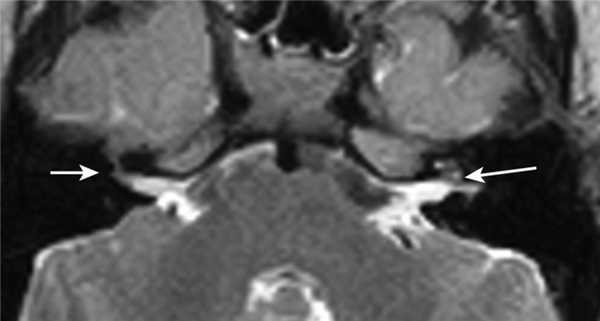

Один пациент, по данным КТ, имел двустороннее бульбообразное расширение внутреннего слухового прохода, что явилось рентгенологической находкой, при этом, по данным МРТ, внутриулитковая жидкость с двух сторон определялась в удовлетворительном количестве, патологии VII—VIII пар ЧМН не было.